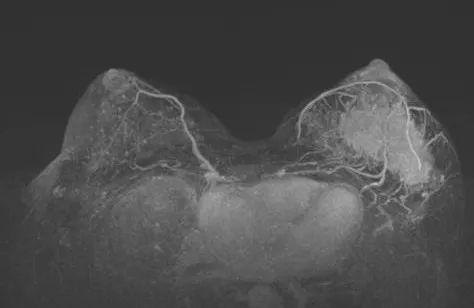

2021-11 乳腺超声:左乳内上象限11点钟至外下象限4点钟方向乳头中央区深面可见一个异常回声区,与导管关系密切,局部延伸至乳头中央区深面,范围约10.5×1.8cm,距皮4mm,形状呈不规则形,边界不清,肿块内部可见丰富紊乱的血流信号。左侧腋窝可见3-4个异常实质回声,大小不等,最大约2.7×1.5cm,形状呈不规则,边界欠清楚。

图1. 新辅助治疗前乳腺超声